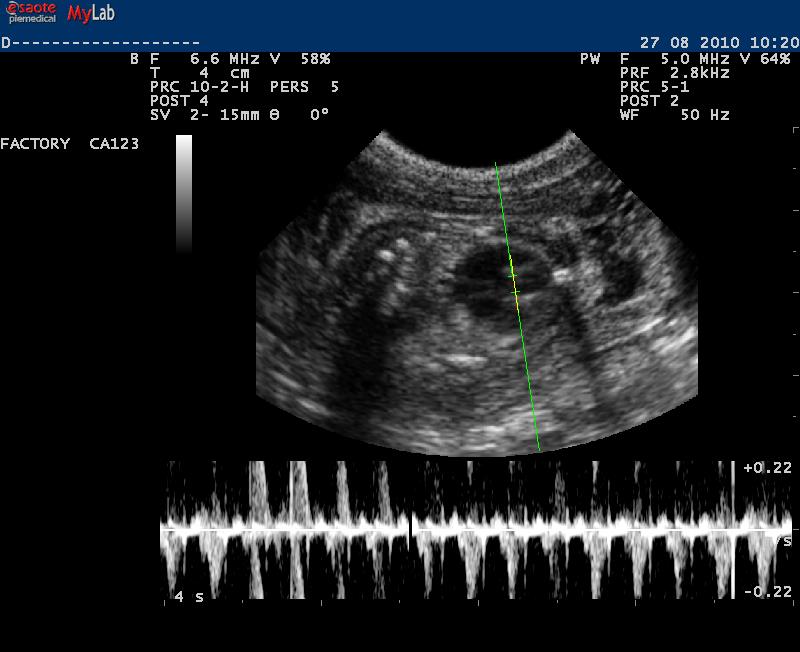

Auch in der Veterinärmedizin wird das schonende Verfahren der Ultraschalldiagnostik zunehmend eingesetzt. Wir verwenden es im Bereich der Abdominal- und Trächtigkeitsdiagnostik .